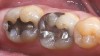

3. Excessive Shear and Tensile Stress Risk Assessment

The third parameter is the risk (or amount) of ongoing shear and tensile stresses that the restoration will undergo, because the prognosis is more guarded for specific materials. All types of ceramics (especially porcelains) are weak in tensile and shear stresses.9 Ceramic materials perform best under compressive stress. If the stresses can be controlled, then weaker ceramics can be used, eg, bonded porcelain to the tooth. The same parameters are evaluated, similar to flexure risk, eg, deep overbites and potentially large areas where the ceramic would be cantilevered (Figure 3). If a high-stress field is anticipated, stronger and tougher ceramics are needed; if por­celain is used as the esthetic material, the restoration de­sign should be engineered with such support (usually a high-strength core system) that it will redirect shear and ten­sile stress patterns to compression. To achieve that, the substructure should reinforce the veneering porcelain by using the reinforced porcelain system, which is generally ac­cepted in the literature as a metal-ceramic concept.10 The practitioner can assess and categorize Low, Medium, or High Risk for tensile and shear stress based on the parameters and symptoms mentioned above.

Figure 3  Image demonstrating a deep overbite in which   shear and tensile stresses would be at least medium. Bonded porcelain would require maintenance of enamel and an occlusal strategy to reduce leverage on the teeth.

Figure 3